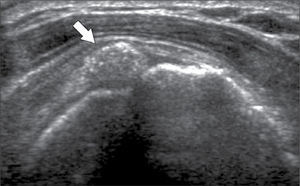

Ecografía de hombroEl US es el examen de primera línea, junto a la radiografía, para la evaluación del hombro doloroso de origen periarticular.

En operadores entrenados (8) permite una buena evaluación de los tendones del manguito rotador, incluso comparable con la RM (9) en busca de tendinosis, tendinopatía cálcica y roturas (figuras 2-4).

En el tendón de la porción larga del biceps es útil para estudio de tenosinovitis o luxación. En articulación acromioclavicular podemos encontrar compromiso degenerativo o inflamatorio, derrame, quistes periarticulares o signos indirectos de disyunción. Se visualiza el receso articular glenohumeral posterior en búsqueda de derrame y también los planos musculares periarticulares. La bursitis subacromiodeltoidea se manifiesta como engrosamiento y/o líquido en la bursa (figura 5). La evaluación dinámica permite observar fenómenos de pinzamiento por el ligamento coracoacromial y también pinzamiento subacromial a la bursa o los tendones.